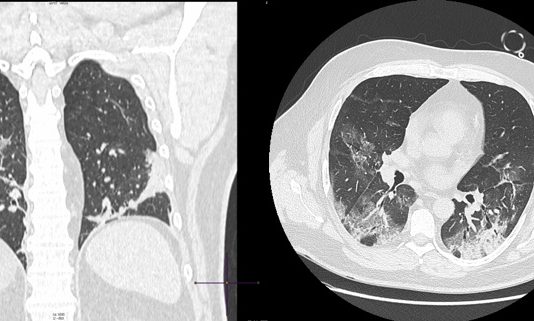

Uomo 63 anni, nessuna comorbidità nota. Febbre e tosse non produttiva. Leucocitosi. Insufficienza respiratoria ipossemica e ipocapnica. Contatto con soggetti zona rossa. Tampone positivo NCOV 19.

HRTC Torace

Figura 1